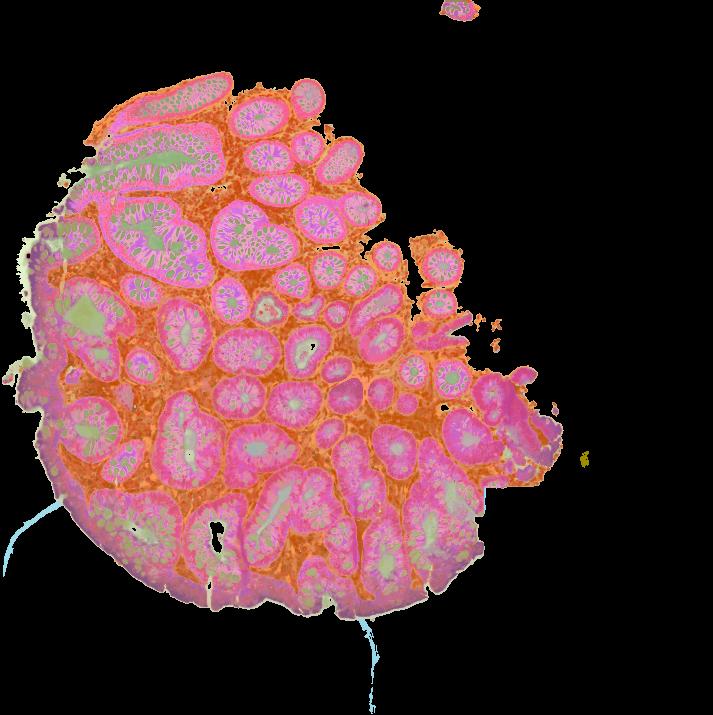

Colorectal cancers (CRCs) arise from precursor polyps whose cellular origins, molecular heterogeneity, and immunogenic potential may reveal diagnostic and therapeutic insights when analyzed at high resolution. We present a single-cell transcriptomic and imaging atlas of the two most common human colorectal polyps, conventional adenomas and serrated polyps, and their resulting CRC counterparts. Integrative analysis of 128 datasets from 62 participants reveals adenomas arise from WNT-driven expansion of stem cells, while serrated polyps derive from differentiated cells through gastric metaplasia. Metaplasia-associated damage is coupled to a cytotoxic immune microenvironment preceding hypermutation, driven partly by antigen-presentation differences associated with tumor cell-differentiation status. Microsatellite unstable CRCs contain distinct non-metaplastic regions where tumor cells acquire stem cell properties and cytotoxic immune cells are depleted. Our multi-omic atlas provides insights into malignant progression of colorectal polyps and their microenvironment, serving as a framework for precision surveillance and prevention of CRC.